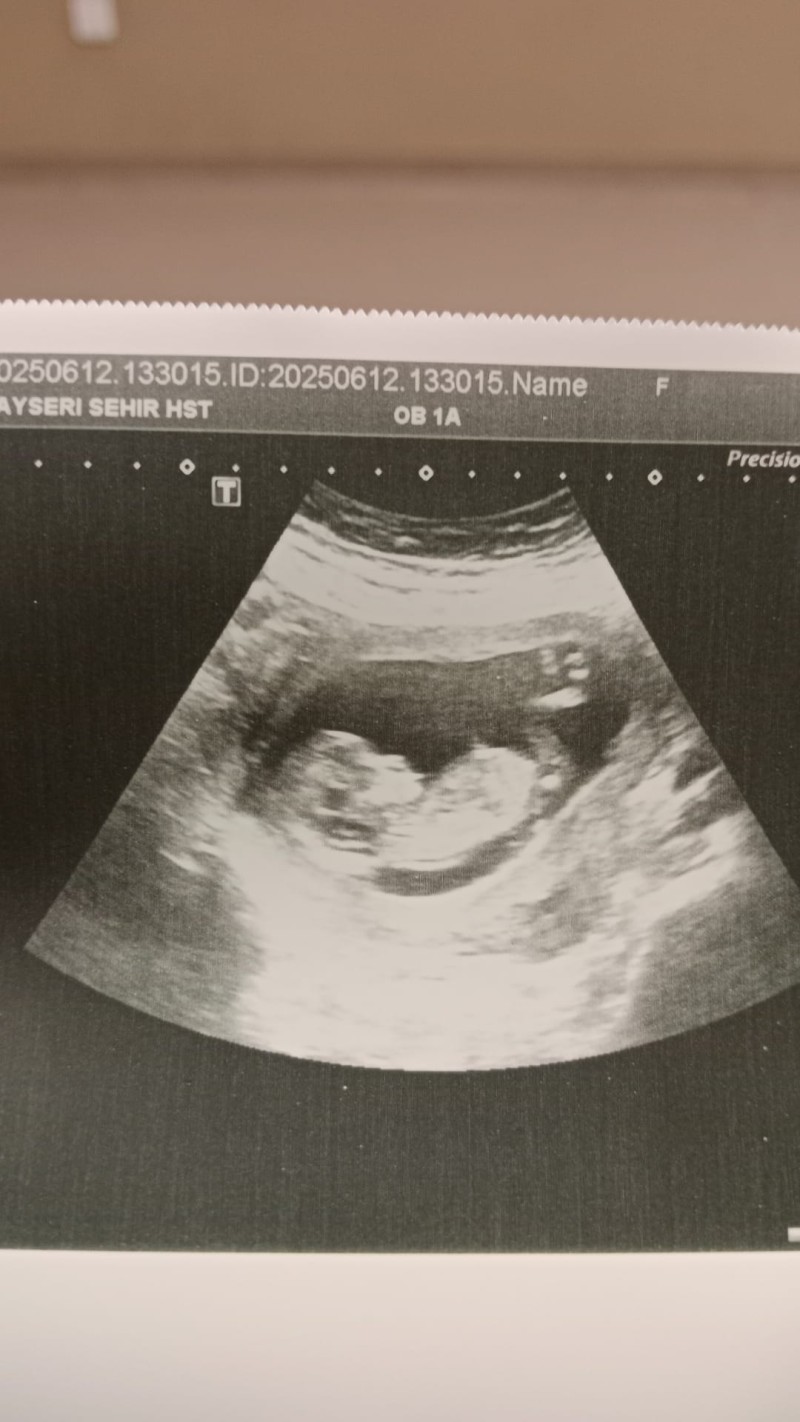

14+2 haftalık 2. gebeliğim  3 yaşında oğlum var arkadaşlar cinsiyetini merak ediyorum doktor net değil daha diyerek söylemedi anlayan varsa bakabilir misiniz rica etsemm teşekkürler 🌸🌸